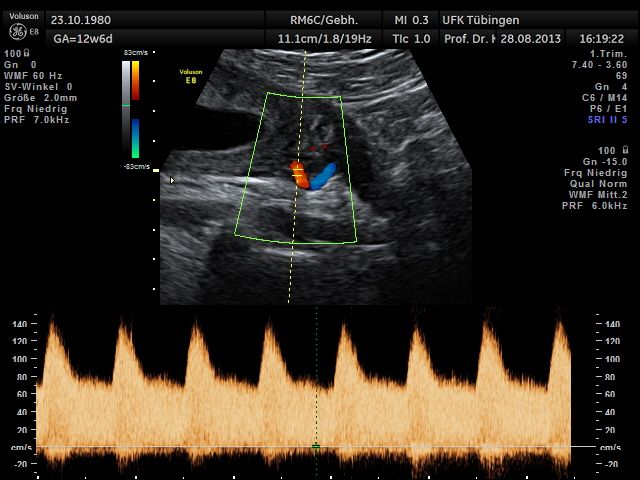

Bauchwanddefekt

Mithilfe des Ersttrimester-Screenings kann das persönliche Risiko einer Präeklampsie bestimmt werden. Dazu wird die Vorgeschichte der Schwangeren, der aktuelle Blutdruck, das Ergebnis der Ultraschalluntersuchung (Widerstand in den Gebärmutter-nahen Gefäßen) und der Blutabnahme bei Ihnen (PAPP-A) kombiniert. Sollte das Risiko über 1:100 sein, empfehlen wir die tägliche Einnahme von Aspirin 150mg bis zu 35.SSW und eine gezielte Überwachung der weiteren Schwangerschaft.

Das Ergebnis der Ultraschalluntersuchung ist wegweisend. Dabei wird der Fet vermessen, die Organe werden untersucht und die sonographischen Marker zur Risikoberechnung für Chromosomenstörungen werden beurteilt. Das sind: die Nackentransparenzdicke, Nasenbein sowie der Blutfluss in der rechten Herzhälfte und im Ductus venosus, einem Gefäß in der Leber des Feten.